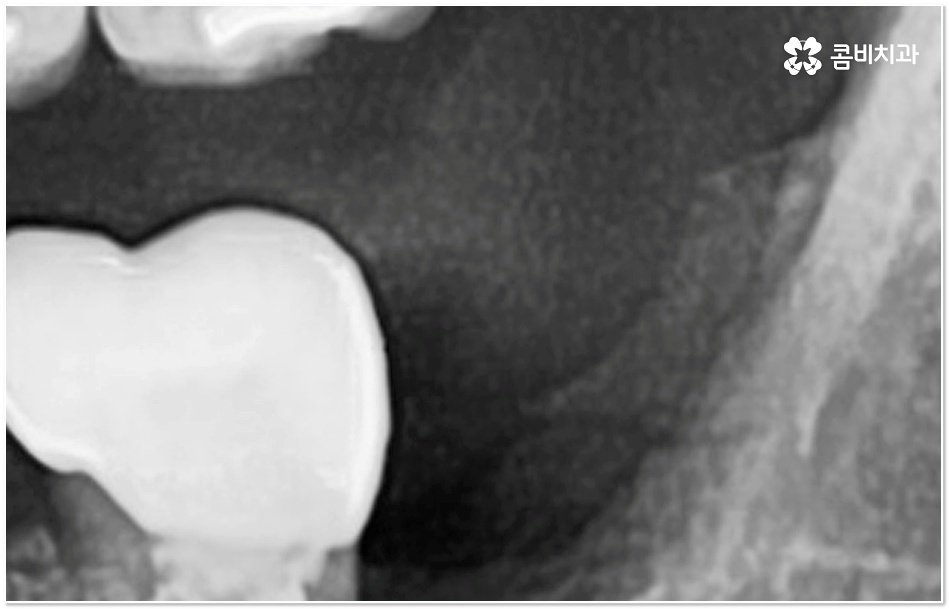

특히 그 중에서도 사랑니와 어금니 사이에 생긴 치아 사이 충치 는 구강 내 가장 안 쪽에 있기 때문에 제 때 발견하기도 어렵고 위치상 치료하기가 쉽지 않아서 병증의 진행 여부 및 상황에 따라 사랑니 뿐만 아니라 어금니까지 발치를 해야 하는 안타까운 상황에 이를 수도 있으니 그 전에 알맞은 대처를 해 주시는 것이 필요할 거예요.

사랑니와 어금니 인접면에 치아 사이 충치 가 발생할 경우 육안으로도 보기 힘들 뿐 아니라 엑스레이를 찍었을 때에도 쉽게 발견하기 힘들 수 있기 때문에 초기에 알아차리지 못하고 치료 시기를 놓치는 경우가 종종 생기며 손상 정도가 많이 심각하거나 위치상 사랑니 발치 후에도 뿌리 끝 염증이 매우 심하거나 치아 사이 충치 로 손상이 심해 치료가 불가능한 케이스의 경우 불가피하게 어금니까지 발치를 해야 할 수 있으므로 이와 같은 상황에 이르지 않도록 평상시에 정기 검진을 꼬박꼬박 받아주는 것이 조기 대처 및 예방 등에 있어 여러 모로 유리하다고 할 수 있습니다.

특히 사랑니가 나오는 시기인 10대 후반부터 20대 초반에 3D CT와 같은 정밀 진단 장비를 통해 사랑니 검진을 한 번 꼼꼼하게 받아보시고 구강 상태를 세세하게 파악한 뒤 비스듬하게 누워있거나 잇몸뼈 속에 매복이 되어 앞 어금니 및 전체 구강 건강에 좋지 않은 영향을 지속적으로 줄 수 있는 상황이라고 판단이 된다면 발치 계획을 세워서 미리 뽑아주는 것도 좋을 거예요.